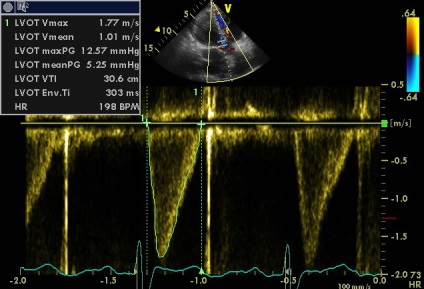

az aortabillentyű áramlási

2. fokozott gradiens aortabillentyű (18.57) és megközelítőleg azonos VTI LVOT VTI Ao és úgy kell értelmezni, egyszerűen következtében tachycardia?

2. megnövekedett gradiens aortabillentyű (18.57) és megközelítőleg azonos VTILVOTi VTIAosleduet értelmezni egyszerűen következtében tachycardia?

Tachycardia idején szkennelés nem (a klip jobb alsó sarkában a csatorna EKG monitorozás szívritmus alakzatnak, akkor változik a 73-77 perc). De érszűkület (akár minimális) szintén nem (igazad van), és enyhe növekedés sebessége és a színátmenet összefüggésbe hozható a megnövekedett perctérfogat (verőtérfogat LV). „Körülbelül egyenlő a VTI” csak beszélni a közelítő egyenlőség a terület és a terület AK BT LV (aorta regurgitatio nem számít, mert még kicsi, annak ellenére, hogy az alacsony PHT. Ebben az esetben a gyorsított összehangolás LZH- Ao nyomás nem jár gyors növekedése a diasztolés nyomás a bal kamrában, mint a súlyos aorta regurgitáció, és a gyors nyomás csökkenése az aortában miatt ürítőnyílás a sipoly).

Qs 30,6h 3,14 x (2,2 \ 2) 2 = 4,94 x 30,6 = 116,3 (azaz megnövekedett, amint fent már említettük)